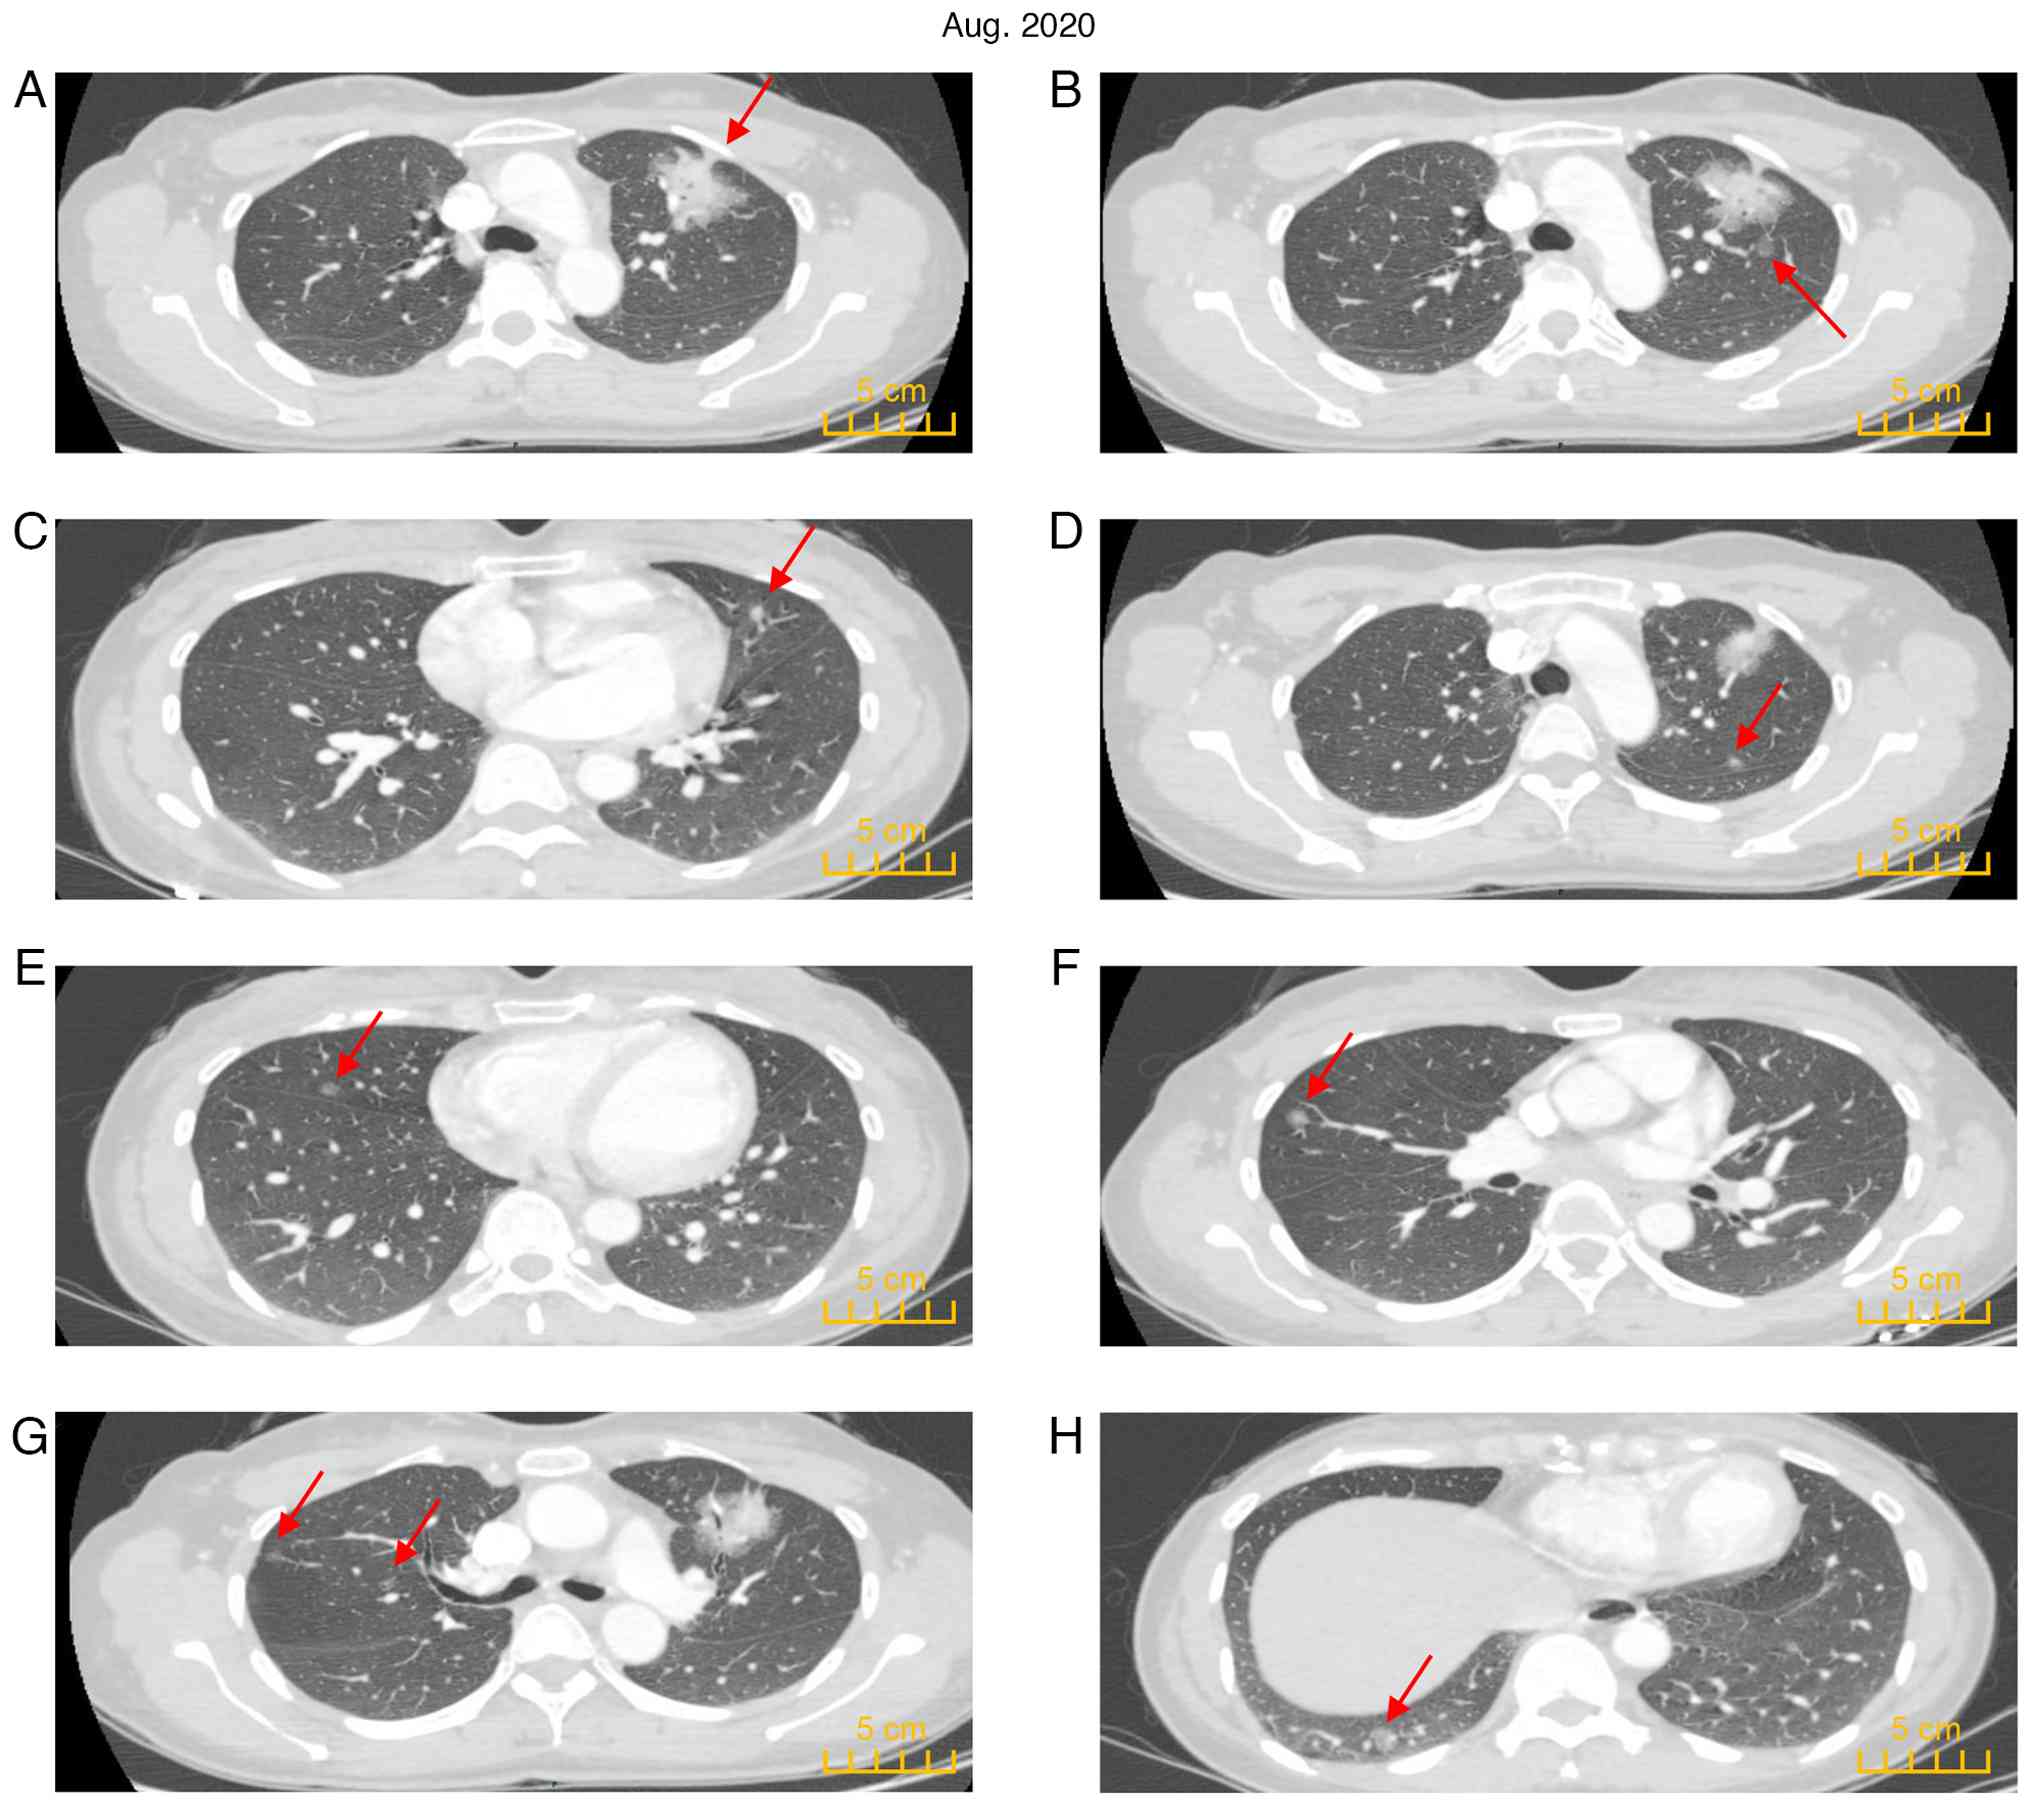

A 45-year-old female patient was admitted to the Affiliated Hospital of Guangdong Medical University (Zhanjiang, China) in August 2020 following detection of multiple nodules in both lungs during a CT scan (Fig. 1). The purpose of the visit was to clarify the pathology of lung lesions and provide adequate treatment. The patient had no specific medical symptoms, such as cough, sputum or fever. The patient did not smoke and had no family history of cancer. Chest-enhanced CT indicated a solid mass shadow (4.6x4.0 cm) in the irregular part of the anterior segment of the left upper lobe with blurred edges, visible lobulation, spiculation and cavitation signs, local pleural traction signs, irregular bronchial stenosis and occlusion in the lesion. Enhanced scanning indicated apparent enhancement of the solid component of the lesion (Fig. 2A). Multiple ground-glass nodules (GGN) and mixed ground-glass nodules were scattered in both lungs (Fig. 2B-H). No apparent abnormalities were noted by brain enhanced MRI. The levels of carcinoembryonic antigen, squamous cell carcinoma antigen, neuron-specific enolase and cytokeratin fragment were all within the normal range. Pulmonary function retest indicated forced expiratory volume in 1 sec (FEV1) of 2.37 l, FEV1% (measured value/predicted value) of 91.62%, forced vital capacity (FVC) of 2.88 l, FVC% (measured value/predicted value) of 94.46% and FEV1/FVC 82.84%. Whole-body PET-CT revealed an anterior left upper lobe lesion with increased F18-fluorodeoxyglucose (FDG) metabolism [maximum standardized uptake value (SUVmax)=7.3] (Fig. 3A and B). No abnormal increase in FDG metabolism was found in the other multiple lesions (Fig. 3C-H). Peripheral lung cancer in the anterior segment of the upper lobe of the left lung was considered. The results suggested the presence of MPLC, and no distant metastasis was noted. The patient was only 45 years old and their son was young and required care. The patient was anxious after learning that they may have late-stage lung cancer and urgently sought diagnosis and treatment. Following multidisciplinary discussions, a high possibility for a primary tumor was considered and surgical treatment was recommended. The patient and their family agreed to receive surgical treatment.

PET-CT images of the patient. (A and

B) Hypermetabolism was observed in the left upper lung lesion

(maximum standardized uptake value=7.3). (C-H) No abnormal increase

in F18-fluorodeoxyglucose metabolism was found in the

other multiple lesions.

Figure 3

PET-CT images of the patient. (A and B) Hypermetabolism was observed in the left upper lung lesion (maximum standardized uptake value=7.3). (C-H) No abnormal increase in F18-fluorodeoxyglucose metabolism was found in the other multiple lesions.